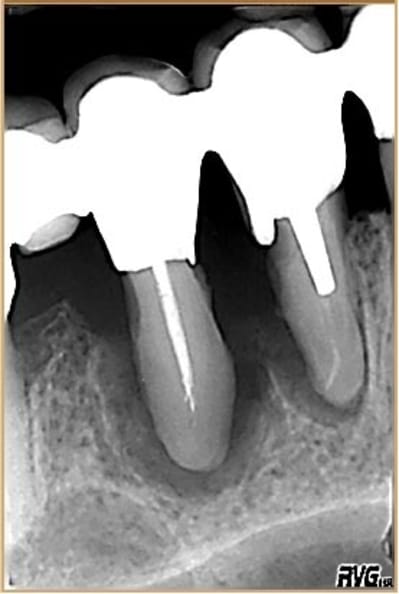

J'ajouterai que sans connaître l'âge du patient on peut constater que la chambre pulpaire est assez rétractée par rapport aux dents adjacentes, avec peut être des pulpolithes, en tous cas une activité dentinaire pouvant signifier une agression pulpaire, non ?

Cette dent présente encore des signes d'hyperfonction (elargissment ligamentaire sur la racine distale) . Donc il faut encore retoucher à l'occlusion qui est un facteur aggravant la déminéralisation et qui empeche la reminéralisation .

concernant la vitalité de la dent ,perso je serai très prudent à l'avenir car la pulpe même vivante a souffert et sur le moyen terme il peut y avoir des soucis (cela m'est arrivé ) . il faut attendre encore au moins 4 à 5 mois pour réévaluer l'espace inter radiculaire .par contre en mésial , il est possible qu'il persiste un système d'ancrage collagénique cele semble se densifier . Pas de sondage pas toucher pour le moment .

Il y aura certainement aussi un petit problème d'espace inter radiculaire residuel à gérer car il persistera entre l'espace inter radiculaire et le niveau osseux mesial interdentaire un décalage. Ce n'est forcemment un problème si la patiente gère bien son controle de plaque.